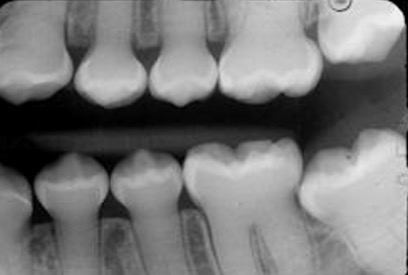

Enamel hypoplasia

-Incomplete formation of the enamel matrix during tooth development.

- This can occur due to an illness or high fever.

-Remember there is no such thing as enamel HYPERplasia!